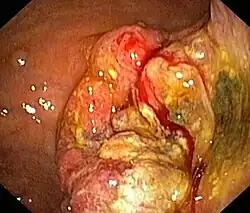

Ramucirumab (IMC-1121B; Handelsname Cyramza) ist ein monoklonaler Antikörper, der in der Therapie von fortgeschrittenem oder metastasiertem Magenkrebs, Kolorektalkarzinom, nicht-kleinzelliges Lungenkarzinom oder Leberzellkarzinom eingesetzt wird.[1]